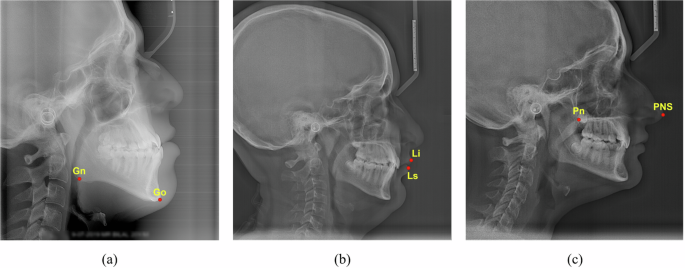

Consequently, we implemented an additional layer of validation, mandating that our expert orthodontists conduct a comprehensive review of the entire dataset. Their primary objective was to verify that no landmarks had been inappropriately interchanged. Our diligence paid off, as this thorough expert review uncovered 8 instances where both the labellers had accidentally swapped the locations of two landmarks. Illustrative examples of these landmark swaps are presented in Fig. 6, demonstrating the importance of comprehensive, expert-level review in maintaining dataset integrity.

A visualization of the perils of mislabelling caused by swapped landmarks, exemplifying how two labellers accidentally swapped the locations of two landmarks, even though they were correctly marked in their respective positions. (a) shows the case where gonion (Go) was swapped with gnathion (Gn) (b) illustrates labrale inferius (Li) being switched with labrale superius (Ls) (c) presents posterior nasal spine (PNS) being swapped with pronasale (Pn).